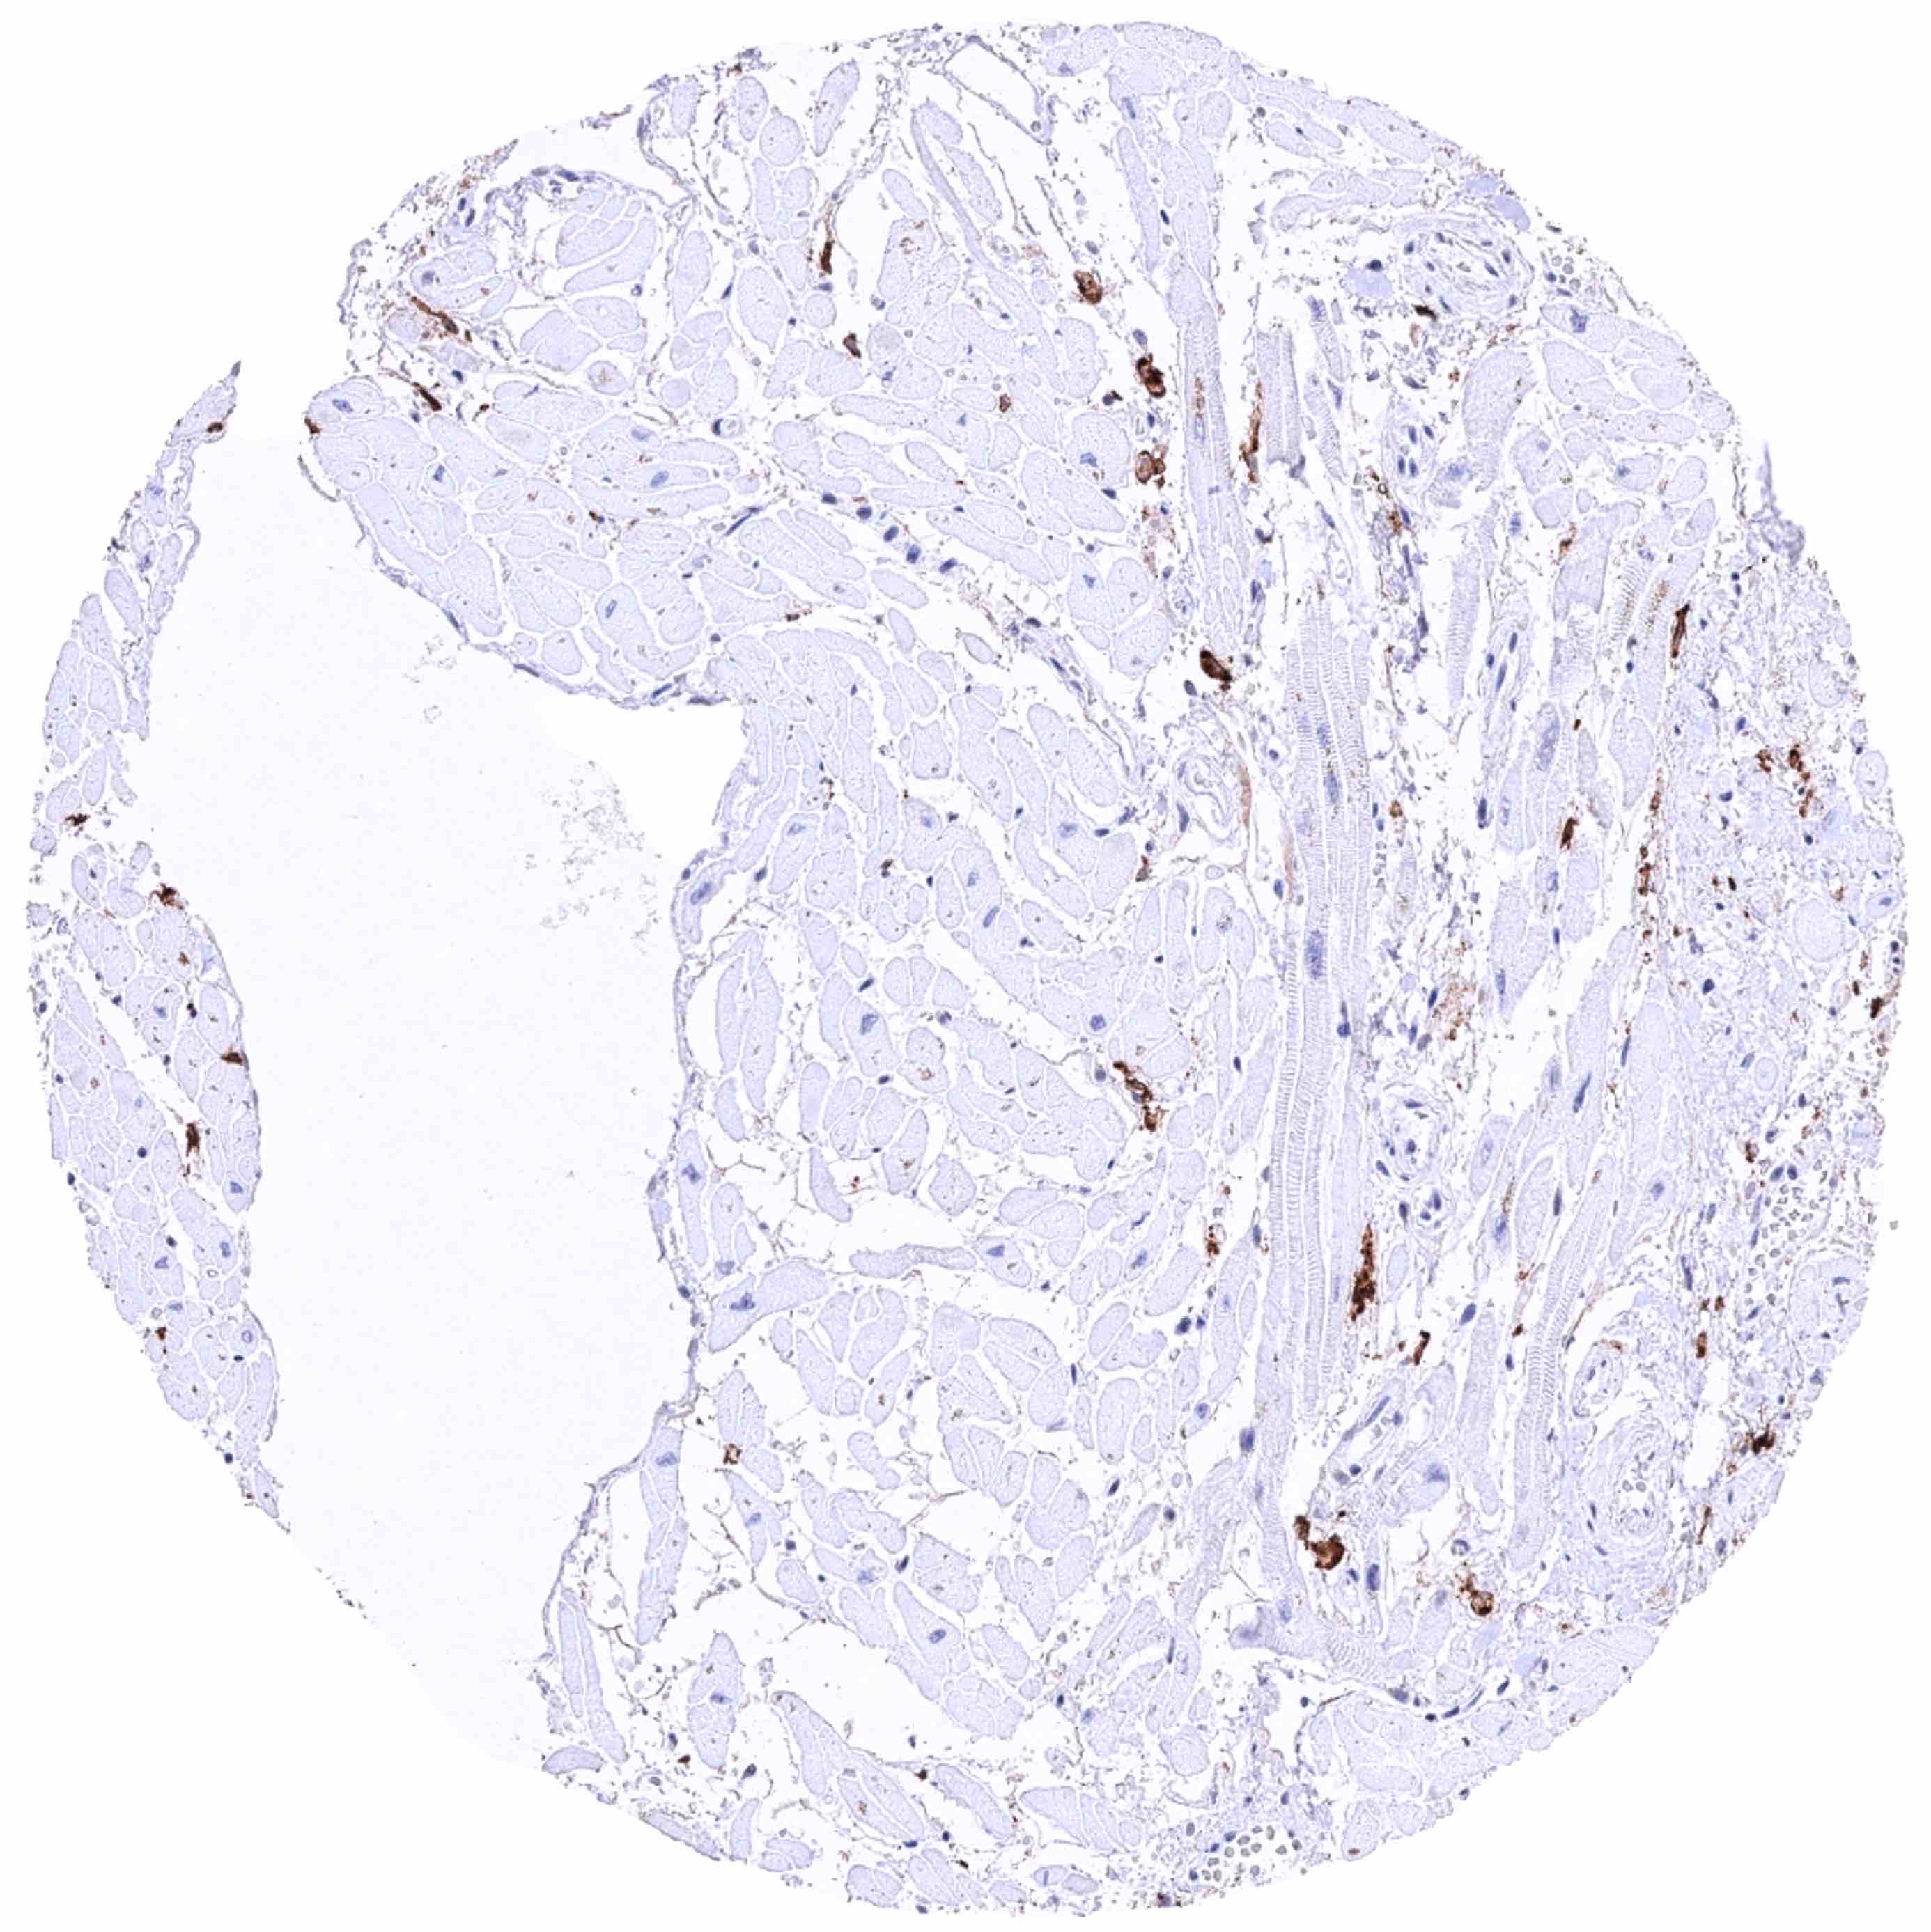

Skeletal muscle – Strong CD38B staining of a fraction (not of all!) of endothelial cells in small vessels